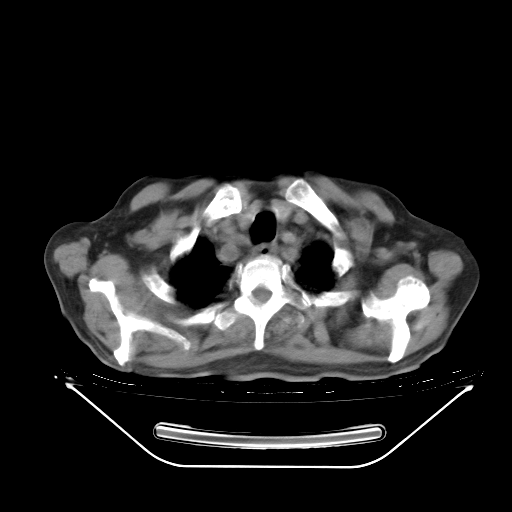

今天复查肺部CT,发现双肺广泛磨玻璃样改变。所以我把3月19日和5月9日相隔50天的肺部CT上传。请大家会诊。

2009年3月19日肺部CT片。

5月9日肺部CT(在4月27日齐鲁医院肺部CT描述部分肺组织磨玻璃样改变,12天后肺组织广泛磨玻璃样改变)